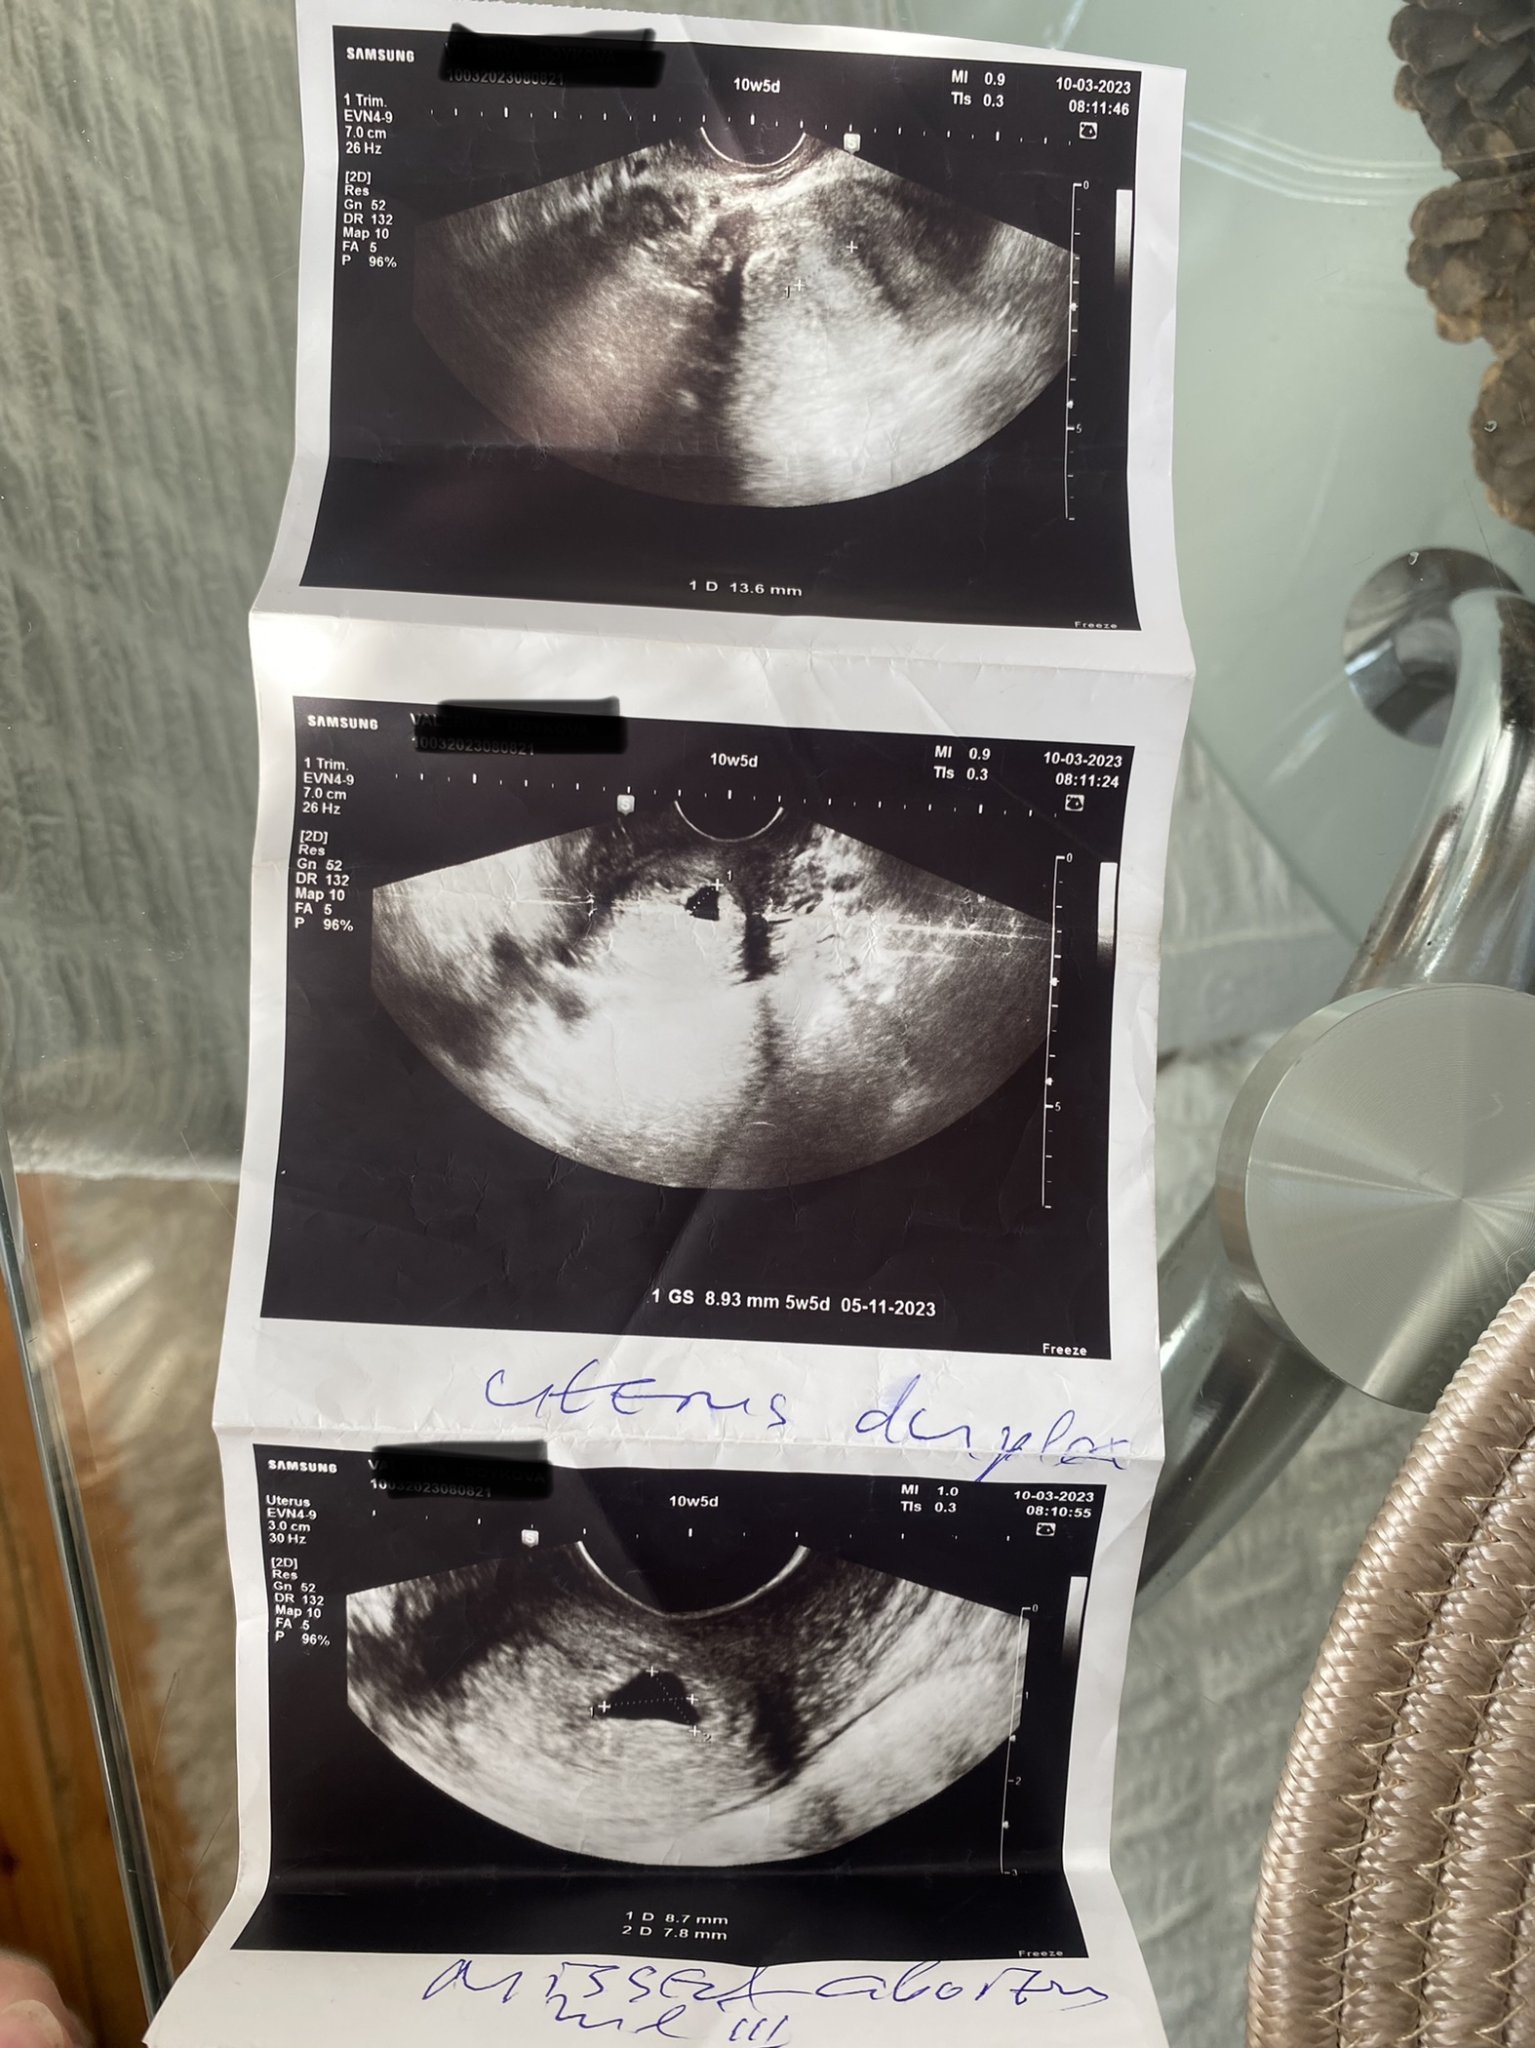

на 22.01.2023г. имах положителен тест за бременност. Запазих час при гинеколог за следващата седмица, но се оказа твърде рано, за да се види нещо и на последващата пак отидох за преглед (две седмици след положителен тест) Тогава се видя сак отговарящ на 5седмици и 5 дни. Каза да си запазя час отново след месец, за да чуем сърцето и видим ембриона. Пиех дуфастон и фолиева киселина. Няколко дни преди прегледа късно вечерта прокървих леко и отидох в моя роден град в спешния кабинет. Гинеколога при който ходя е от друг град. Та докторката, която беше на смяна на ехографския преглед видя сака като ми каза, че отговаря на 10 седмица +5 дни, реално в която трябваше да бъда. Но ембрион и сърце няма. Искаше да остана и да прекратим бременността. Аз отказах и на следващата сутрин отидох при моя гинеколог. Но веднага след прегледа започна много по-силно кървене и на сутринта по време на пътя много остри болки. Вече знаех, че няма надежда да е наред тази бременност Sad Гинеколога ми потвърди, че не вижда ембрион, но ми стана странно, че измери сака с размер отговарящ на 5 седмица +1 ден, а преди няма 10 часа в спешния кабинет ми казаха, че е с размер отговарящ на бременността, но без ембрион. Той ми предписа ЦИТОТЕК и да чакаме дали ще се изчисти тялото без кюртаж. След този преглед започна много обилно кървене с остри болки два дни. След това нямах болки и кървенето намаля. Днес е 10 ден след прокървяването, имам много слабо зацапване. Имах един останал тест за бременност, който го направих преди малко и показа две ярки черти, отделно корема ми е много подут и след това прочистване на голямо количество кръв на кг не съм мръднала, даже съм качила още 1кг. ТОй ми предписа по телефона протичозачатъчни, коиъо пия вече 5 ден. Другата седмица ще ходя на преглед да видим какво е станало с изчистването, но ми е странно това с положителния тест + надутия ми корем и качването на кг.